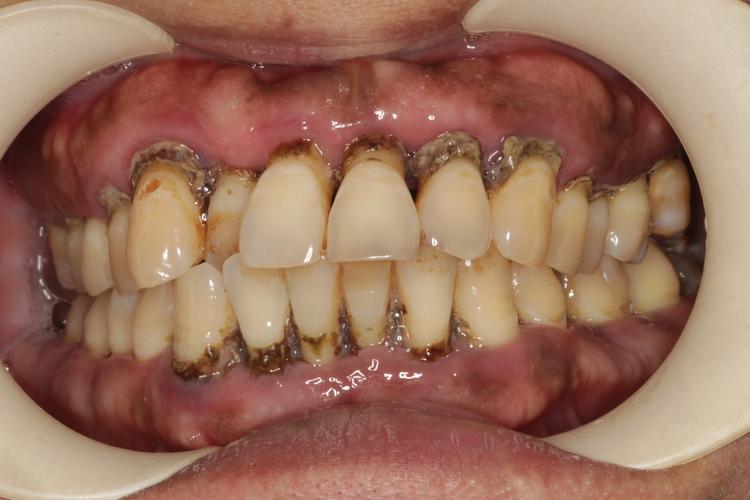

牙周炎是种牙的前提,必须先控制!

(图片来源网络,侵删)- 这是最重要的一点! 牙周炎是牙齿周围组织的炎症,如果不先彻底治疗并控制好炎症,种植牙的长期成功率会大大降低,甚至可能导致种植体周围炎、种植体松动脱落。

- 治疗流程: 需要专业的牙周科医生进行系统治疗,包括龈上洁治(洗牙)、龈下刮治、根面平整、必要时牙周手术等,直到牙周炎症得到控制、口腔卫生维护良好、牙周状况稳定(通常需要数周甚至数月)。